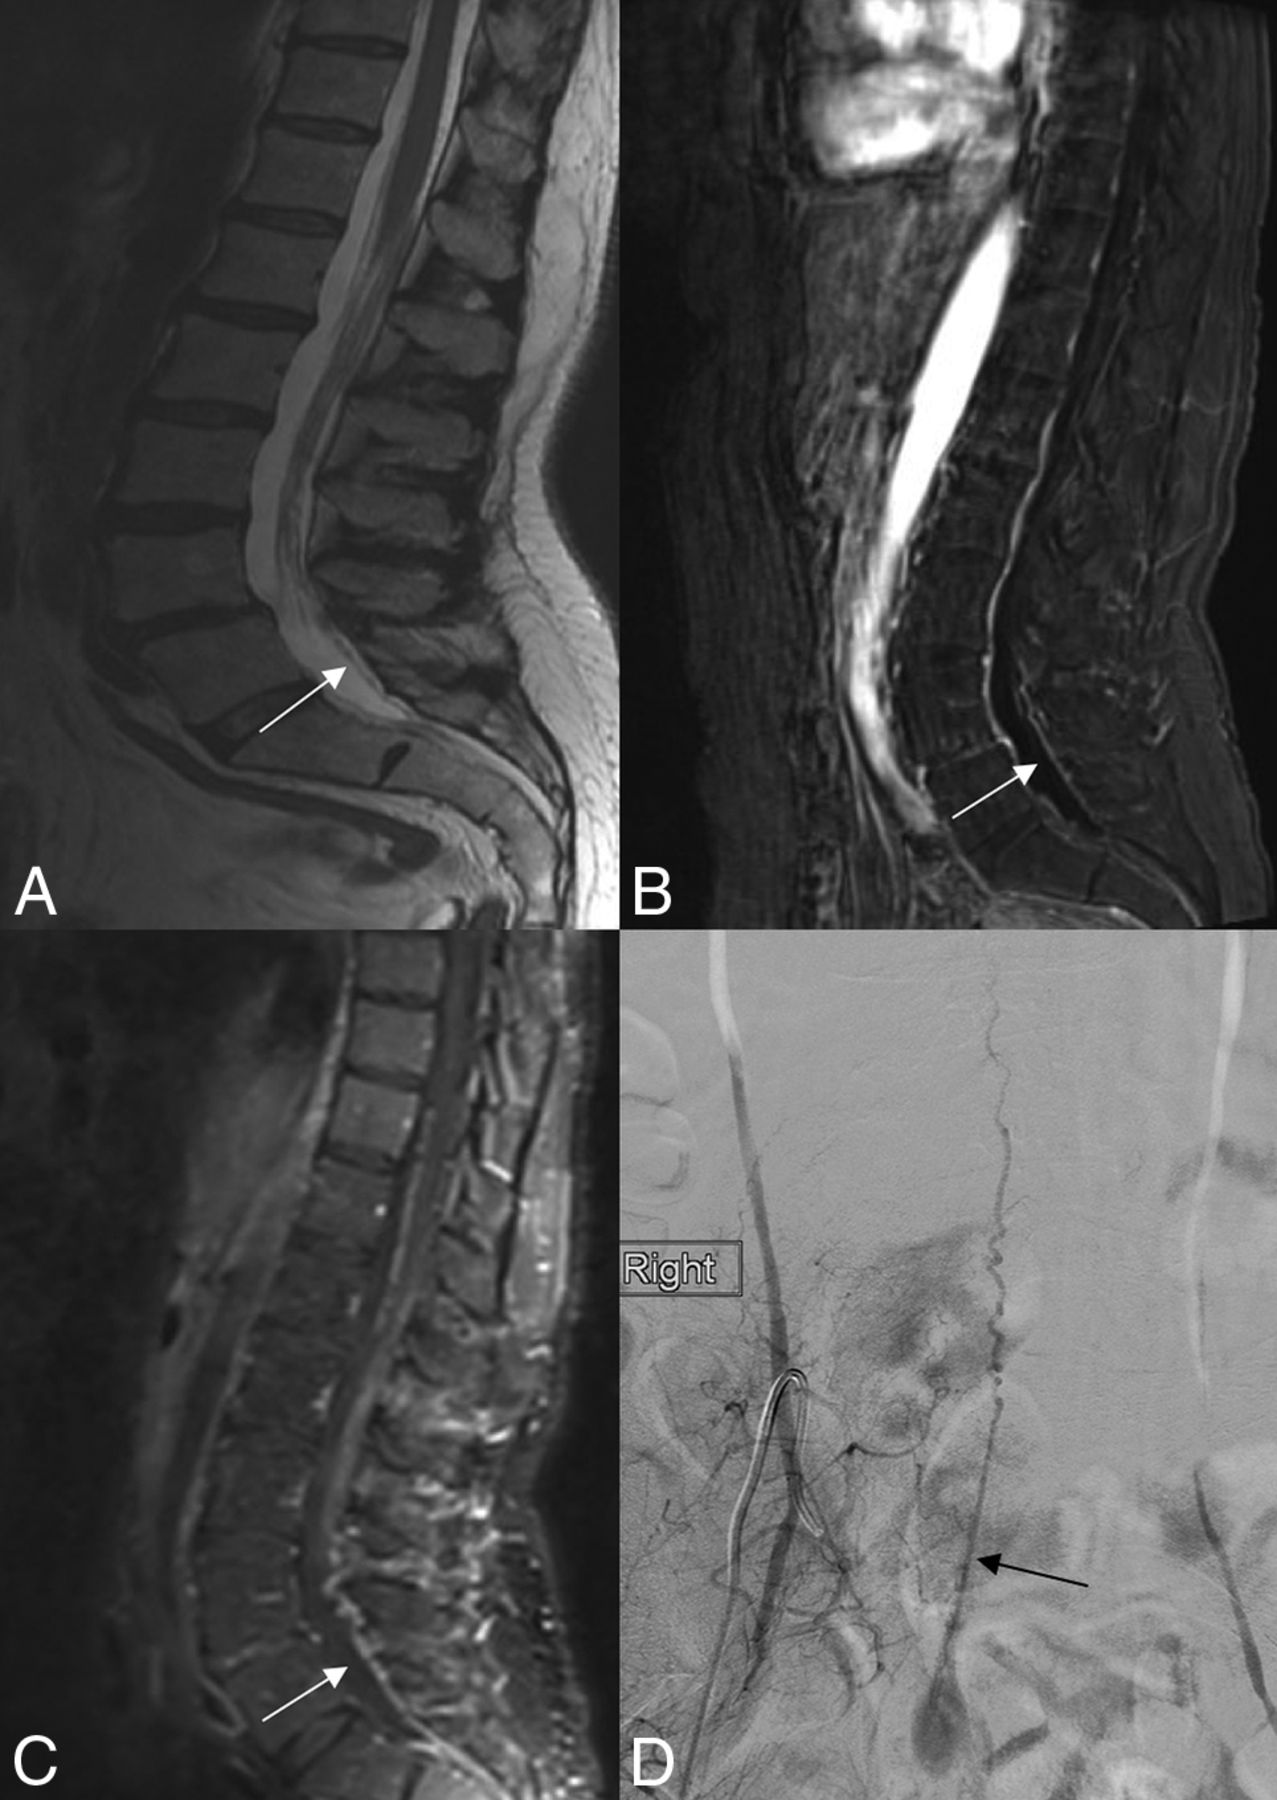

A 75-year-old man with a sacral dural arteriovenous fistula at S1. A, Sagittal T2-weighted MR imaging shows a dilated vein of the filum terminale (white arrow). B and C, Contrast-enhanced MRIs demonstrate marked dilation of the vein of the filum terminale (white arrow). D, Conventional angiogram in the anteroposterior plane following injection into the right internal iliac artery demonstrates a fistula at S1 with a dilated vein of the filum terminale (black arrow).